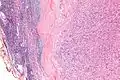

| Micrograph of an intranodal palisaded myofibroblastoma. H&E stain. | |

IPMs are diagnosed by examination of the tissue by a pathologist. They have a rim of peripheral lymphoid tissue (remnant of a lymph node) and consist of spindle cells with nuclear palisading. Red blood cell extravasation is common and blood vessels surrounded by collagen with (fine) peripheral spokes (amianthoid fibers) are usually seen.[2]

Immunostains for smooth muscle actin and cyclin D1 are characteristically positive. The main histologic differential diagnosis is schwannoma.

Low mag.